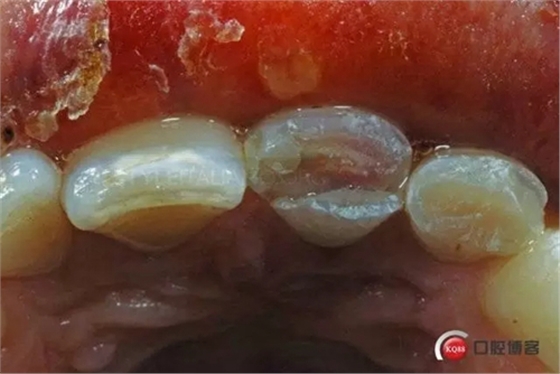

More than 5 mm fracture. Tooth 2.2 is still vital